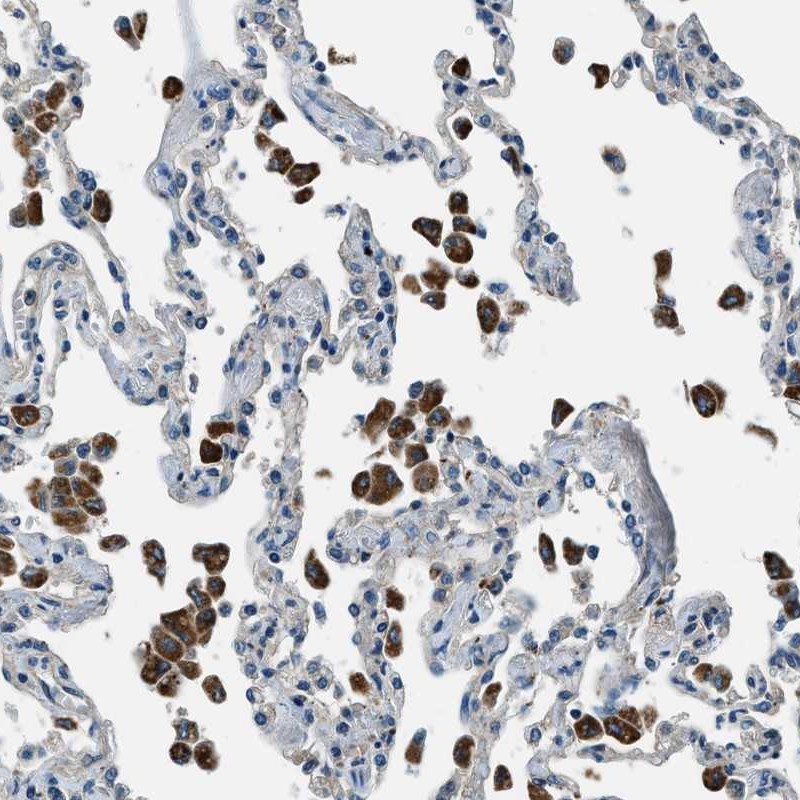

Immunohistochemical staining of human lung shows strong cytoplasmic positivity in macrophages.